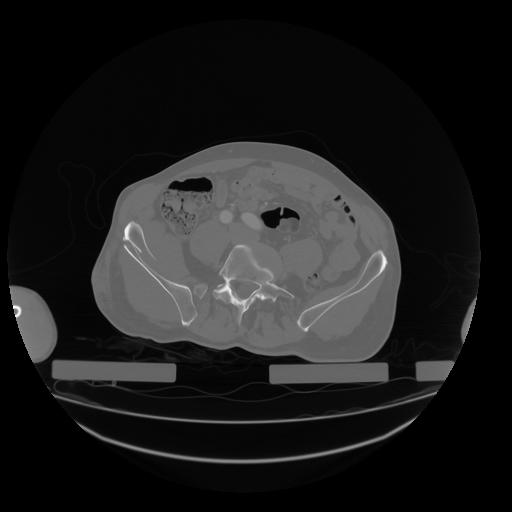

28 CUERPO,CE,Vol,2.0,CUERPO,,